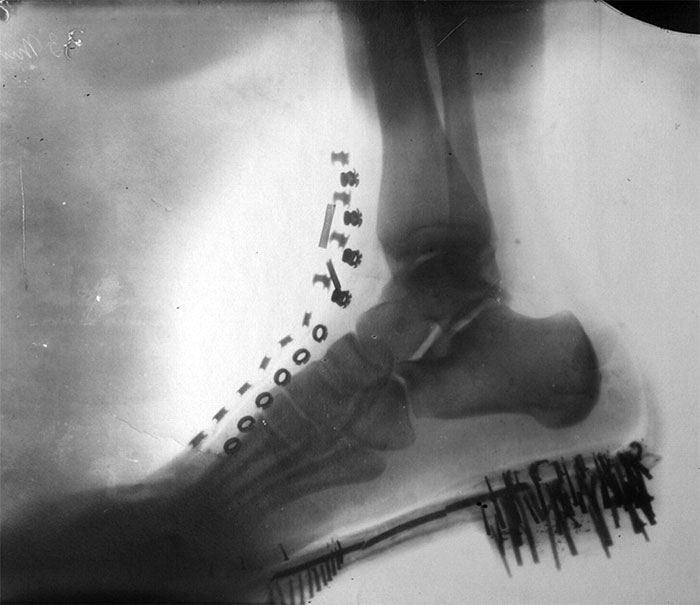

Nikola Tesla's Foot In A Shoe, By Himself. Tesla Obtained The Image In 1896 With X-Rays Generated By His Own Vacuum Tube, Similar To Lenard’s Tube, At A Distance Of 8 Feet